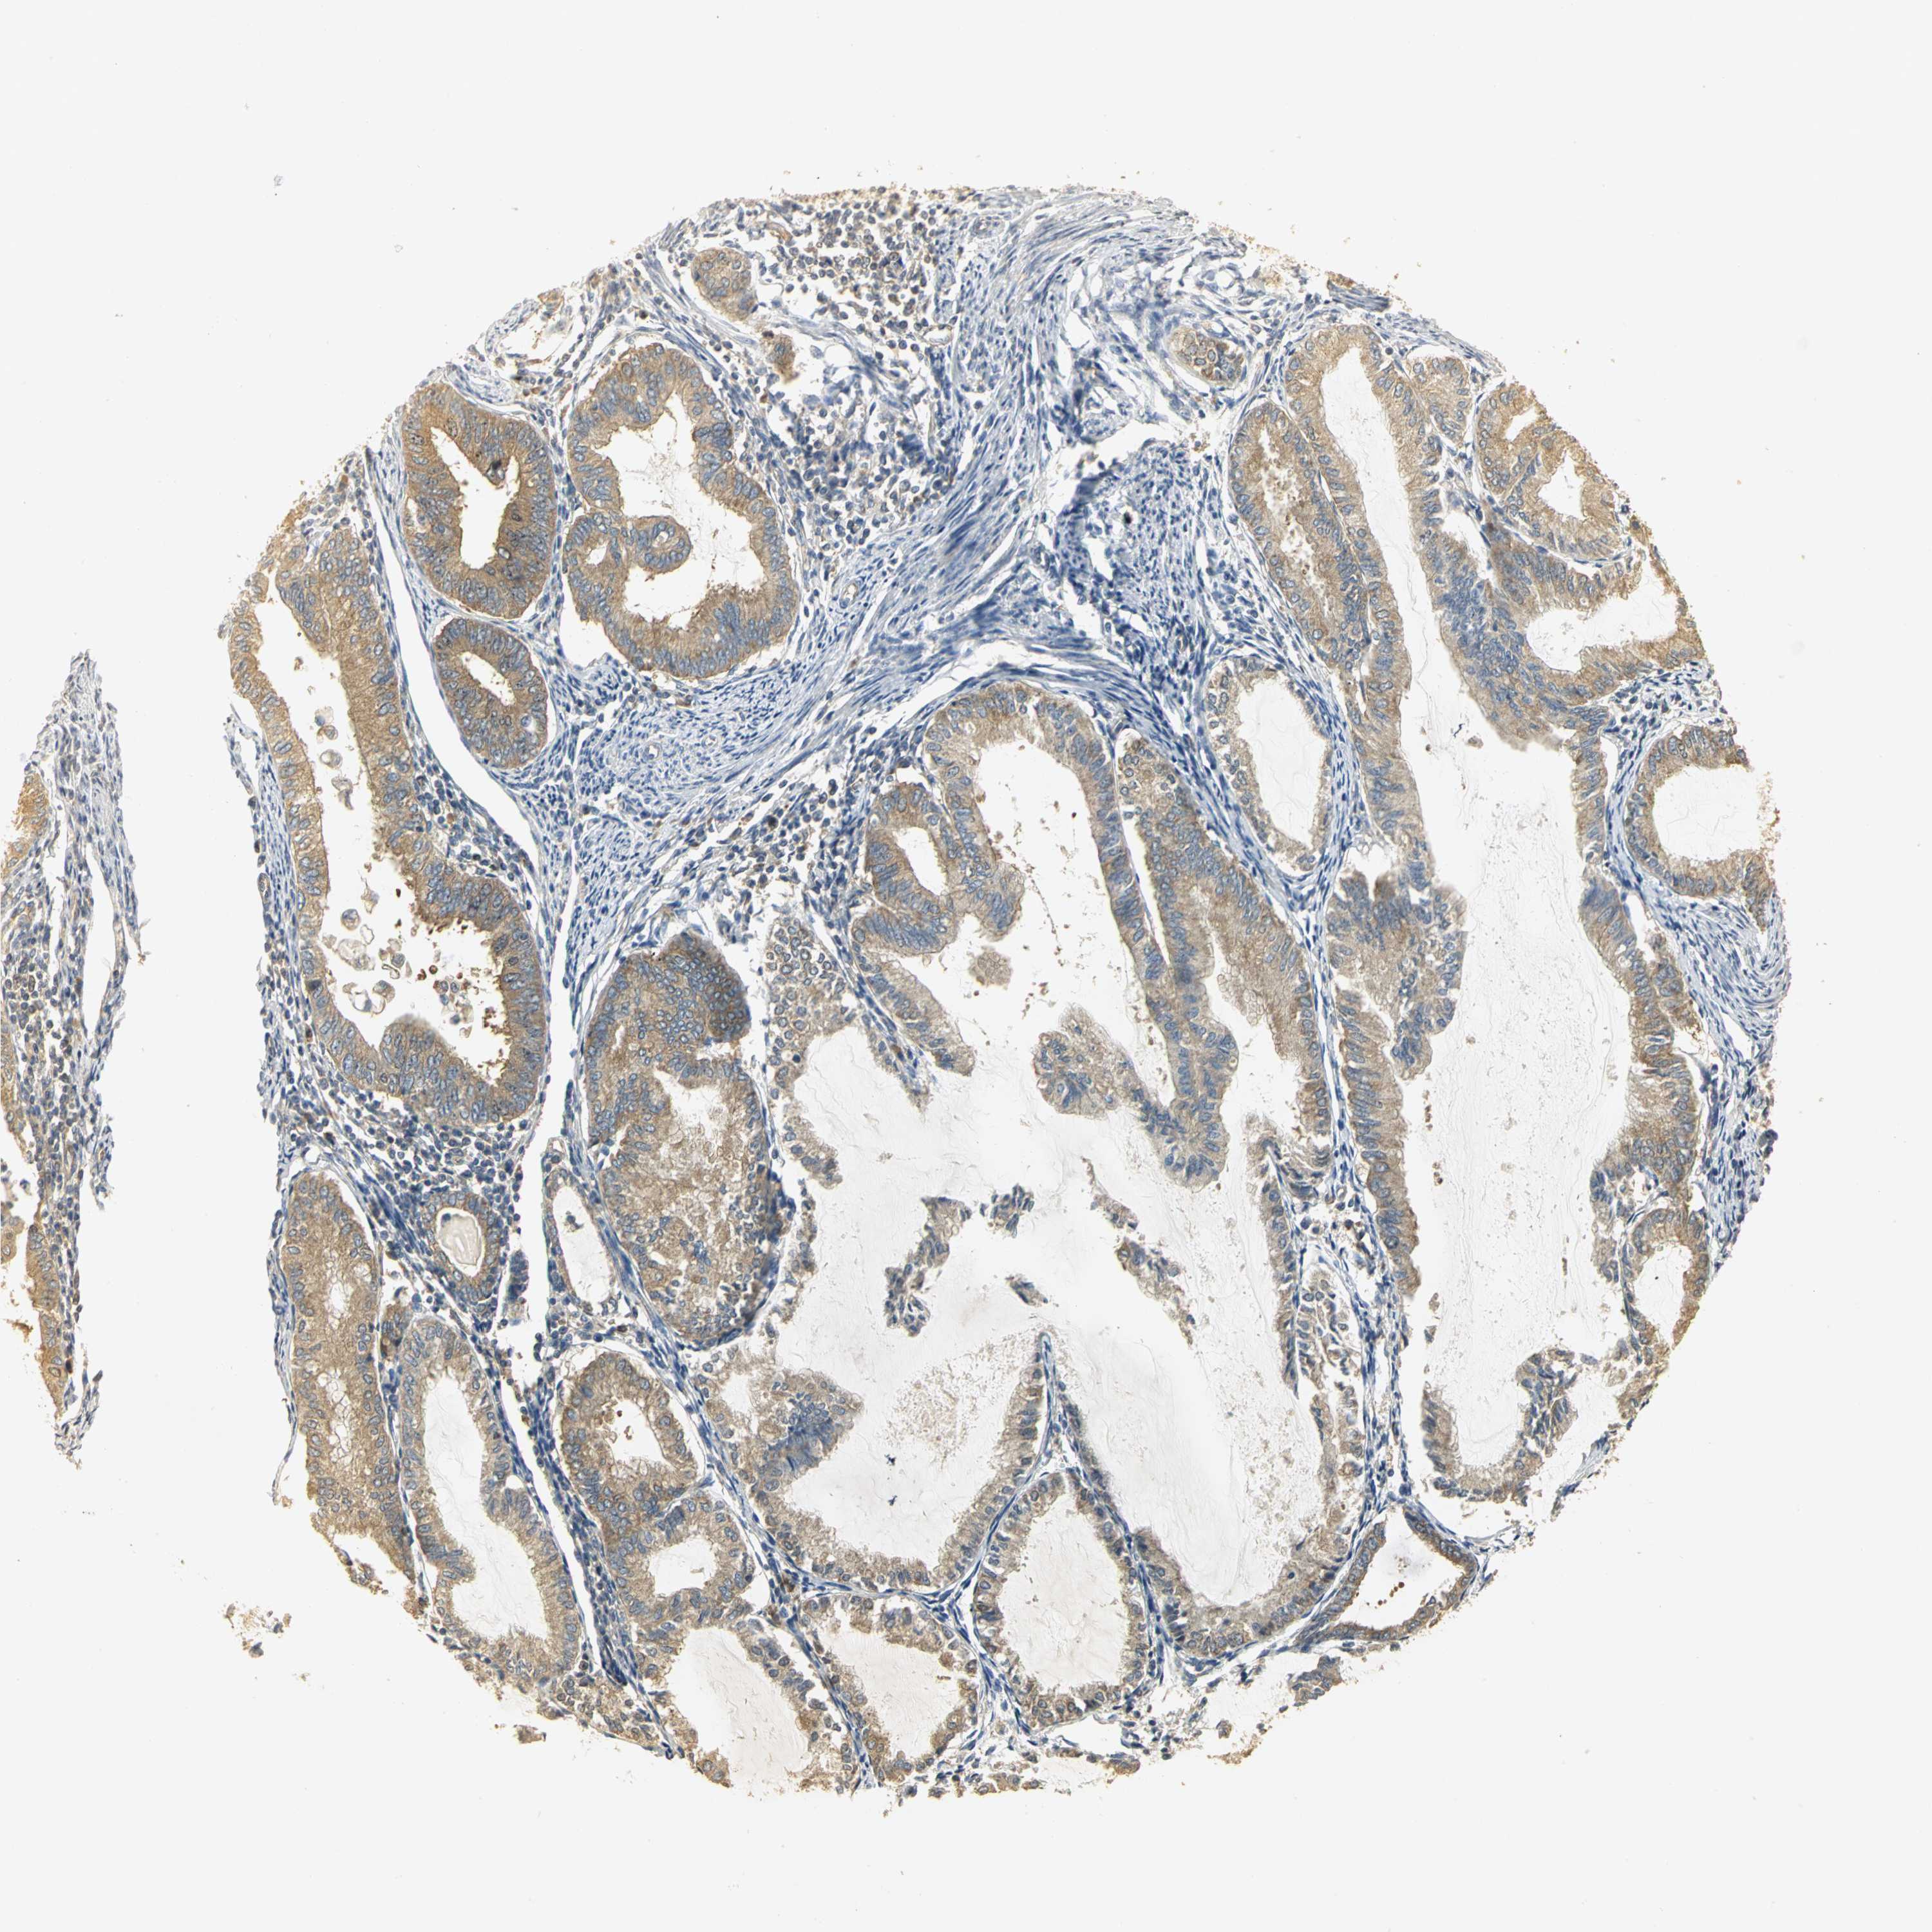

ENDOMETRIAL CANCER - Protein expressioni

A mouse-over function shows sample information and annotation data. Click on an image to view it in a full screen mode. Samples can be filtered based on level of antibody staining by selecting one or several of the following categories: high, medium, low and not detected. The assay and annotation is described here.

Note that samples used for immunohistochemistry by the Human Protein Atlas do not correspond to samples in the TCGA dataset.

Antibody stainingi

Antibody staining in the annotated cell types in the current human tissue is reported as not detected, low, medium, or high, based on conventional immunohistochemistry profiling in selected tissues. This score is based on the combination of the staining intensity and fraction of stained cells.

Each image is clickable and will lead to virtual microscopy that enables deeper exploration of all samples and also displays staining intensity scores, fraction scores and subcellular localization as well as patient and tissue information for each sample.

Antibody HPA003979

Antibody HPA004130

Staining

High

Medium

Low

Not detected

Intensity

Strong

Moderate

Weak

Negative

Quantity

>75%

75%-25%

<25%

None

Location

Nuclear

Cytoplasmic/membranous

Cytoplasmic/membranous,nuclear

Adenocarcinoma, NOS

Neoplasm, malignant, NOS